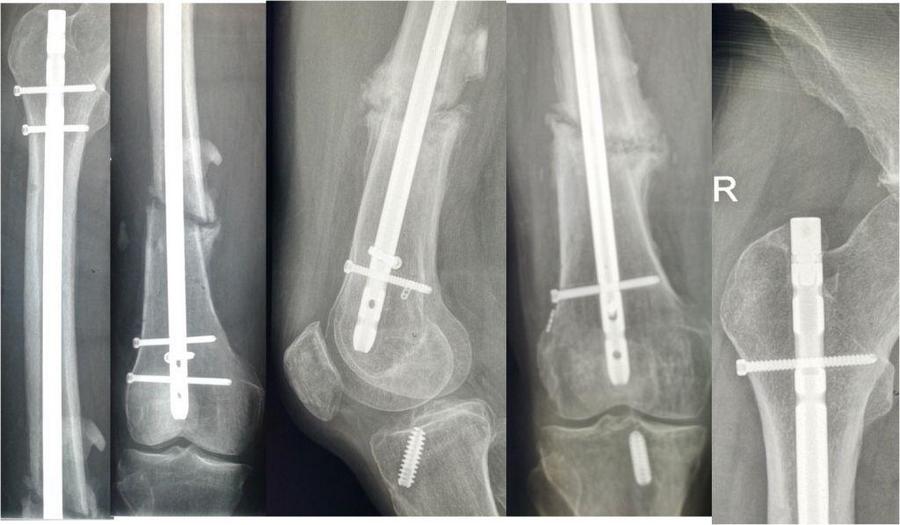

Друзья! Нужен совет! Пациент 47 лет 1 сентября 2016 г, получил сочетанную травмы головы и конечностей, в том числе закрытые переломы плечевой кости и бедра справа При поступлении в клинику выполнен МОС плечевой кости и бедра штифтами. Послеоперационное течение гладкое. Поступил к нам в декабре по поводу замедленной консолидации плечевой кости. При обследовании R-логически признаки формирования костной мозоли на бедре и плече, пальпаторно в области переломов массивные инфильтраты, свидетельствующие о консолидации переломов. Дополнительно выявили разрыв ПКС справа. Выполнена ее пластика с динамизацией бедренного штифта и удалением одного из дистальных винтов на бедре (мешал для проведения бедренного канала). Пациент после операции вертикализирован, болевой синдром при опоре на конечность минимальный. В общем все складывалось перспективно...И вот пациент приехал снова. На плече явные признаки атрофического ложного сустава (снимки выложу позже), и на бедре все складывается не в нашу пользу (во вложении снимки вначале и сейчас). Конечно же вопрос, что делать сейчас с бедром???

В общем-то, не видно большой проблемы удалить гвоздь и закрыто пересинтезировать с рассверливанием и с устранением смещения периферического отломка кнаружи.

Конечно, при синтезе следовало бы установить пару отклоняющих винтов или взять ретроградный штифт. Сейчас, я бы переблокировал штифт проксимально, т.к. потенциала для компрессии в зоне перелома уже нет и разрешил полную нагрузку на конечность. Удачи!

На бедре - поможет только интрамедуллярный реостеосинтез, с рассверливанием.

На бедре удалить проксимальный блокирующий винт и полная нагрузка. На плече костная пластика с использованием трансплантата из крыла подвздошной кости рентгенконтроль через 2,5-3 месяца

На бедре проксимальный блокирующий винт находится в крайнем дистальном положении "компрессионного " отверстия и не позволяет продолжать компрессию в зоне перелома, близкого к поперечному. Избыточной подвижности не будет на фоне уже начавшейся консолидации. БИОС будет работать как "внутренний" аппарат Илизарова. Это будет последней попыткой "малой кровью" решить проблему. Если не будет динамики - удаление штифта, репозиция, рассверливание, штифтование большим диаметром. На плече необходимо радикально убрать рубцовую ткань между обломками, плотно тампонировать канал спонгиозной костью и кортикальными фрагментами. Кортикальной частью продольно распиленного трансплантата перекрыть линию перелома, фиксировать винтами. Как вариант, для дополнительной фиксации можно применить накостный остеосинтез пластиной или спицевой аппарат Илизарова, не удаляя штифта.